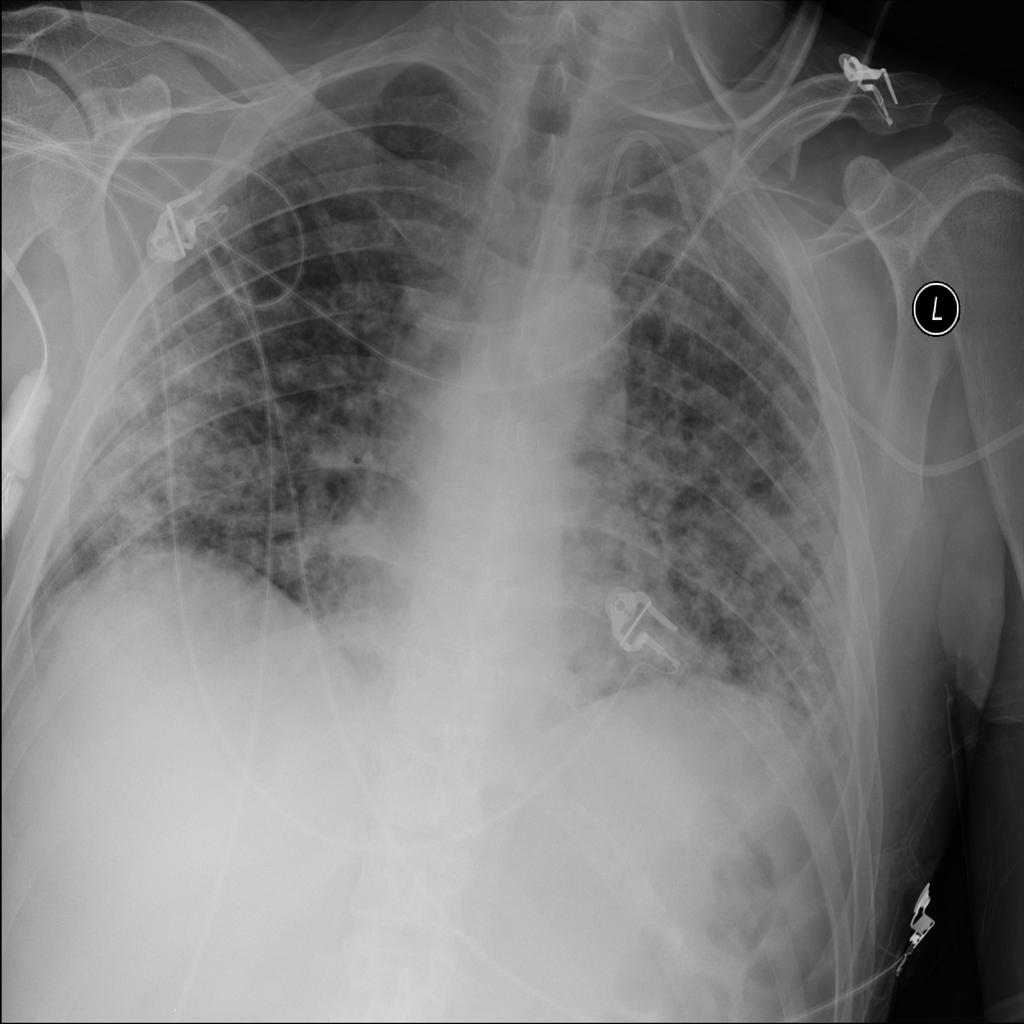

PAT-5B86 · IMG-009Edema

PAT-5B86 · IMG-009

PA